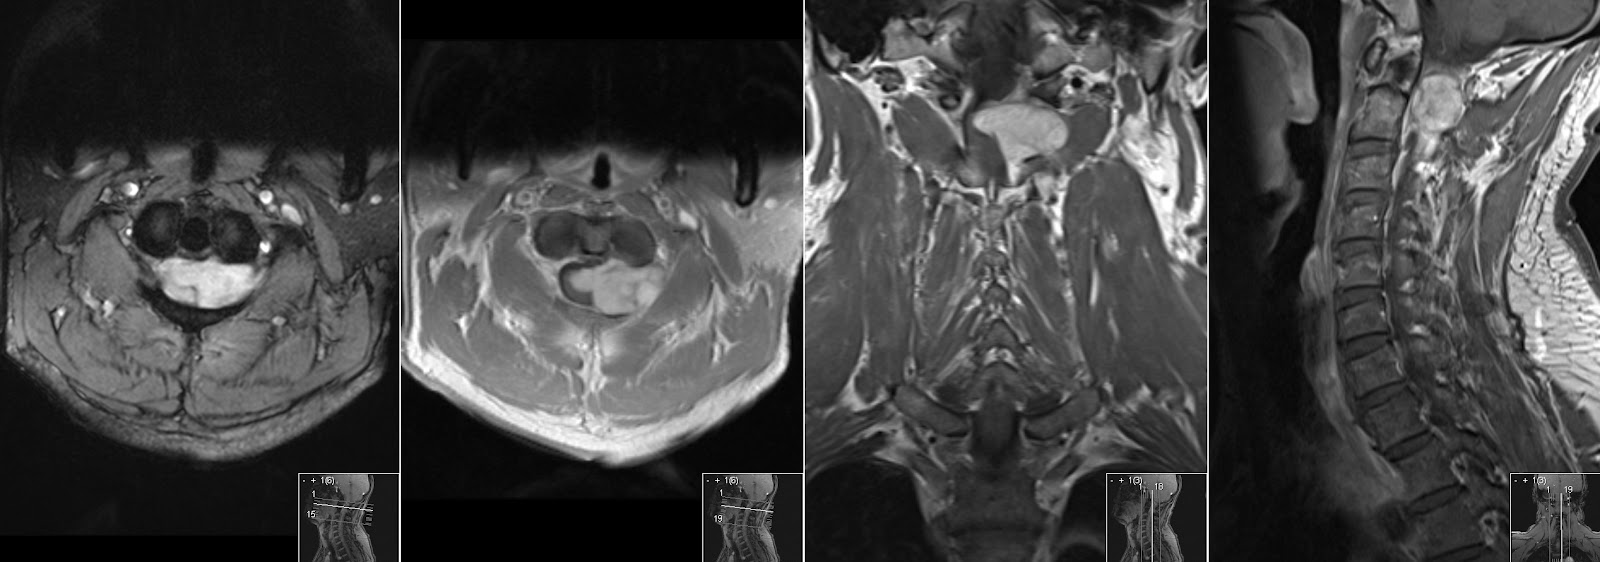

Невринома хвоста

Невринома хвоста 109 фото